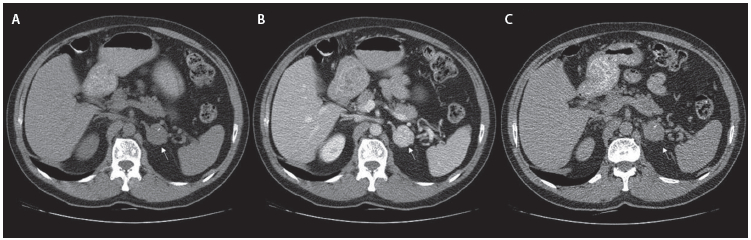

Se solicitó una TC abdominopélvica con contraste que informa un nódulo de 34×30×35 mm en la glándula suprarrenal izquierda, con densidad de tejidos blandos y pequeñas calcificaciones en su interior, que realza de forma homogénea con el medio de contraste. Posteriormente se tomó TC de abdomen con contraste aplicando protocolo para suprarrenales que calcula densidades en fase simple en 35 unidades Hounsfield (UH), 131 UH a los 60 segundos y 63 UH a los 15 minutos, para un lavado absoluto del 72 %. Dada la rápida captación del contraste en la fase arterial, se sugiere el diagnóstico diferencial de feocromocitoma (Figura 1). Adicionalmente se tomó imagen de resonancia magnética (RM) de abdomen, que reportó lesión focal dependiente de cuerpo de glándula suprarrenal izquierda de 31 mm, con contornos lobulados bien definidos, intensidad de señal intermedia en T2 y baja en T1, sin presencia de grasa microscópica en secuencias eco gradiente fuera de fase.

Figura 1. Tomografía de abdomen con protocolo para suprarrenales. La flecha blanca apunta a la lesión en las 3 fases. A. Fase simple. B. Fase arterial temprana a los 60 segundos. C. Fase arterial tardía a los 15 minutos. Se observa un lavado absoluto del 72 %.